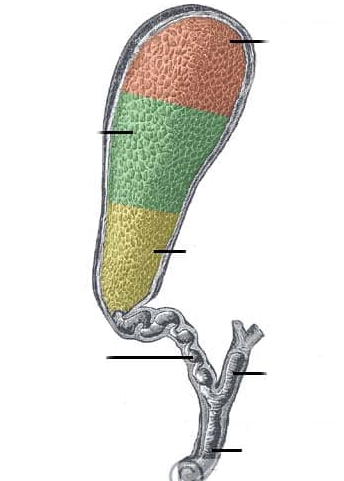

Fundus of gallbladder

orange highlight

Body of gallbladder

green highlight

Neck of gallbladder

yellow highlight

Cystic duct

pink highlight

Left hepatic ducts

Right hepatic ducts

Common hepatic duct

Common bile duct

Duodenal papilla within duodenum